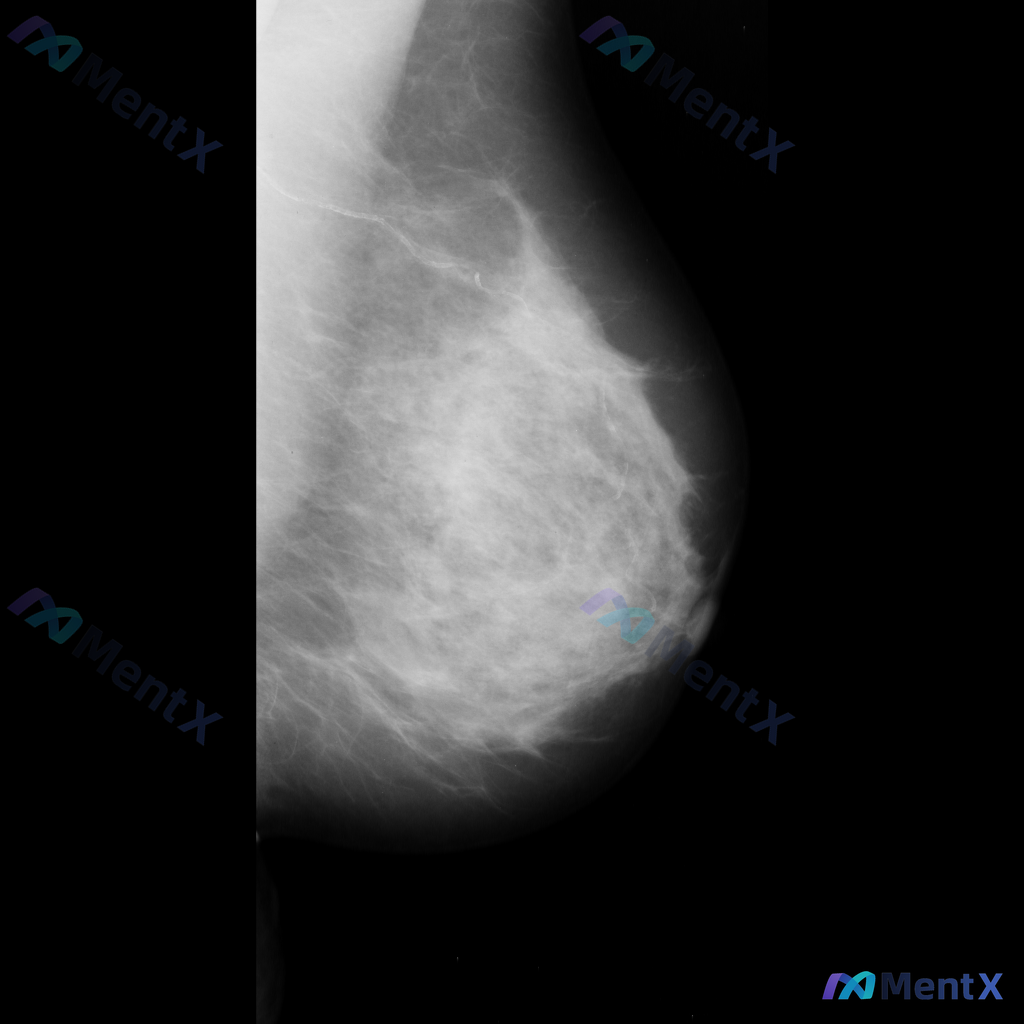

整理了一份乳腺影像的读片资料,想和大家讨论下判断方向: 基本影像信息 - 单侧乳腺X光片,投照体位考虑可能为内外斜位(MLO) - 乳腺组织构成:不均匀致密型 - 影像质量:曝光适中,清晰度良好,无明显伪影 - 可见结构:皮肤、皮下脂肪层、乳头乳晕、Cooper韧带显示尚可;未见明确钙化血管或腋窝淋...

整理到一份单张乳腺钼靶影像的资料,分享给大家讨论: - 背景:乳腺整体为多量腺体型或致密型(BI-RADS C/D型可能) - 主要异常:在乳腺中下部略偏中央区域,可见局灶性不对称密度,或伴有轻度腺体结构紊乱 - 伴随征象:未见明确簇状/线样等可疑恶性钙化,无明确结构扭曲、皮肤增厚/回缩、乳头内陷等...